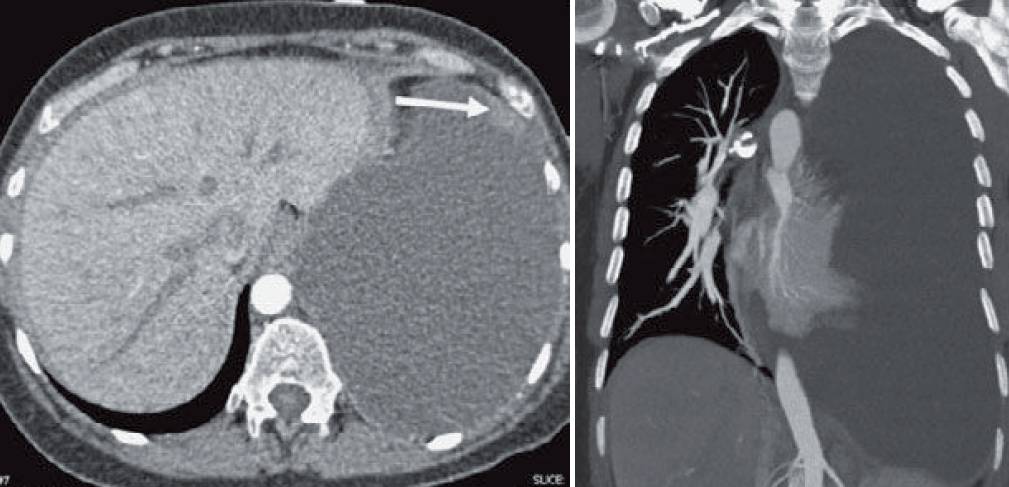

- Two-view chest radiograph (images below) shows increased opacification of the lower and lateral left hemothorax with a meniscus.

- The mediastinum is shift ed rightward and the diaphragm is shifted inferiorly. The mass effect is better seen on the subsequent CT (images below). A small nodule is seen along the anterior pleura (arrow in first image).